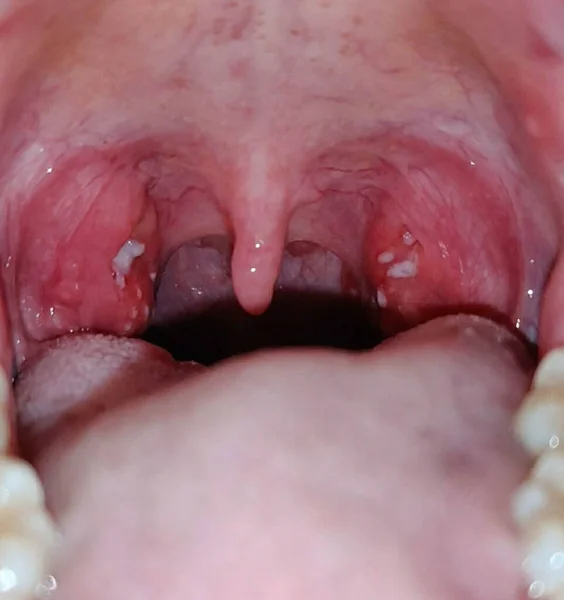

При этом гнойные массы скапливаются в складках миндалин . Это приводит не только к сильным болям, но и к появлению неприятного запаха изо рта .

Симптомы . Жалобы часто сводятся к невралгическим болям, которые отдают в ухо или шею, неприятному запаху изо рта, чувству неловкости или ощущению инородного тела в глотке, боли в миндалинах .

Болевые проявления в области шеи и горла можно ощутить при любых инфекциях, которые провоцируют воспаление миндалин, гортани, а также поражают лимфатические ткани . Простуда, грипп, скарлатина, корь или дифтерия становятся причиной плохого самочувствия, начинает болеть горло, а вскоре вся гортань . Симптомы